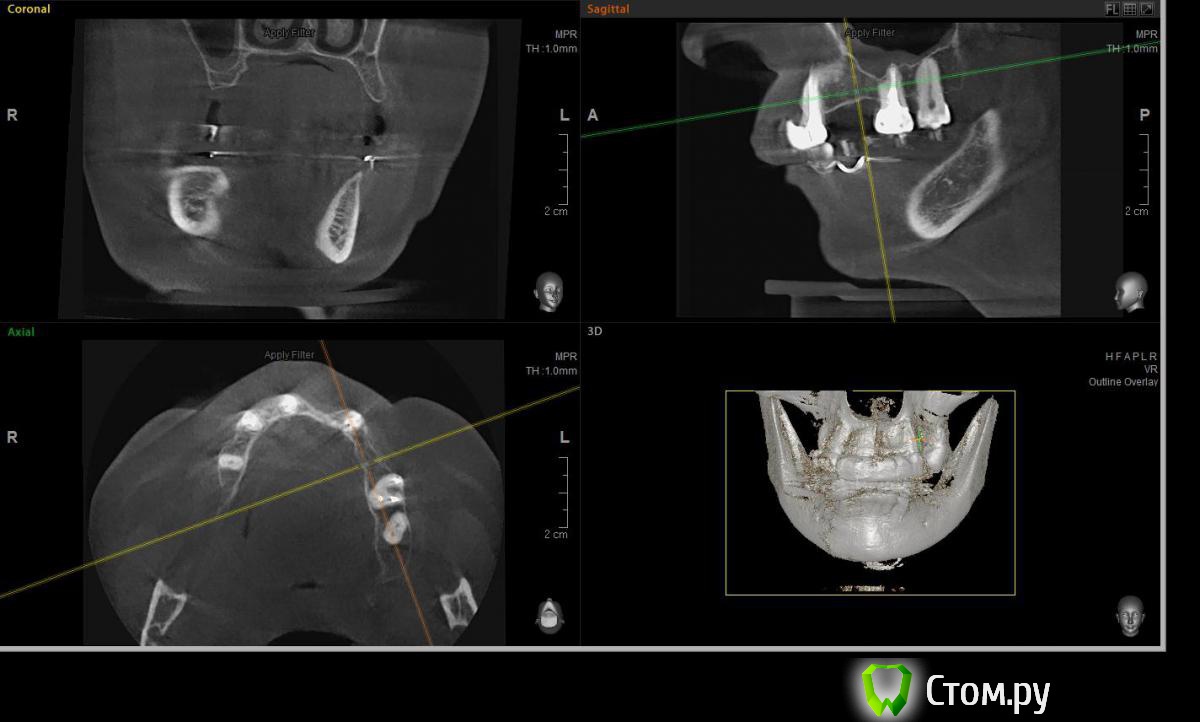

Евгений Ходыкин Опубликовано 23 июля, 2014 Поделиться Опубликовано 23 июля, 2014 Решили с пациенткой пока начать с в.ч. В планах имплантация в область отсутствующих 1.6, 1.4, 1.2, 2.1, 2.2, 2.4, 2.5. С 1.6 самому более менее все понятно, мануальных навыков хватит) Прошу помощи коллег относительно остальных областей. Фронт особливо печален... Забегая наперед скажу, что блоки еще не делал. Ауто точно пока брать не планирую, ибо нет даже теоретических навыков. Хочу начать все-таки с аллоблоков. У кого какие будут мнения, заранее спасибо) Ссылка на комментарий

Bier Опубликовано 24 июля, 2014 Поделиться Опубликовано 24 июля, 2014 потренируйтесь на модели. Выкроить мембрану (возьмите фольгу для тренировки), привинтить нёбно, положить графт (ауто+ксено), завернуть вестибулярно, прикрутить/пристучать. Ссылка на комментарий

Евгений Ходыкин Опубликовано 24 июля, 2014 Автор Поделиться Опубликовано 24 июля, 2014 В области 2.4 выраженная нёбная резорбция. Крепить мембрану туда, или все-равно наращивать вестибулярно?? Ссылка на комментарий